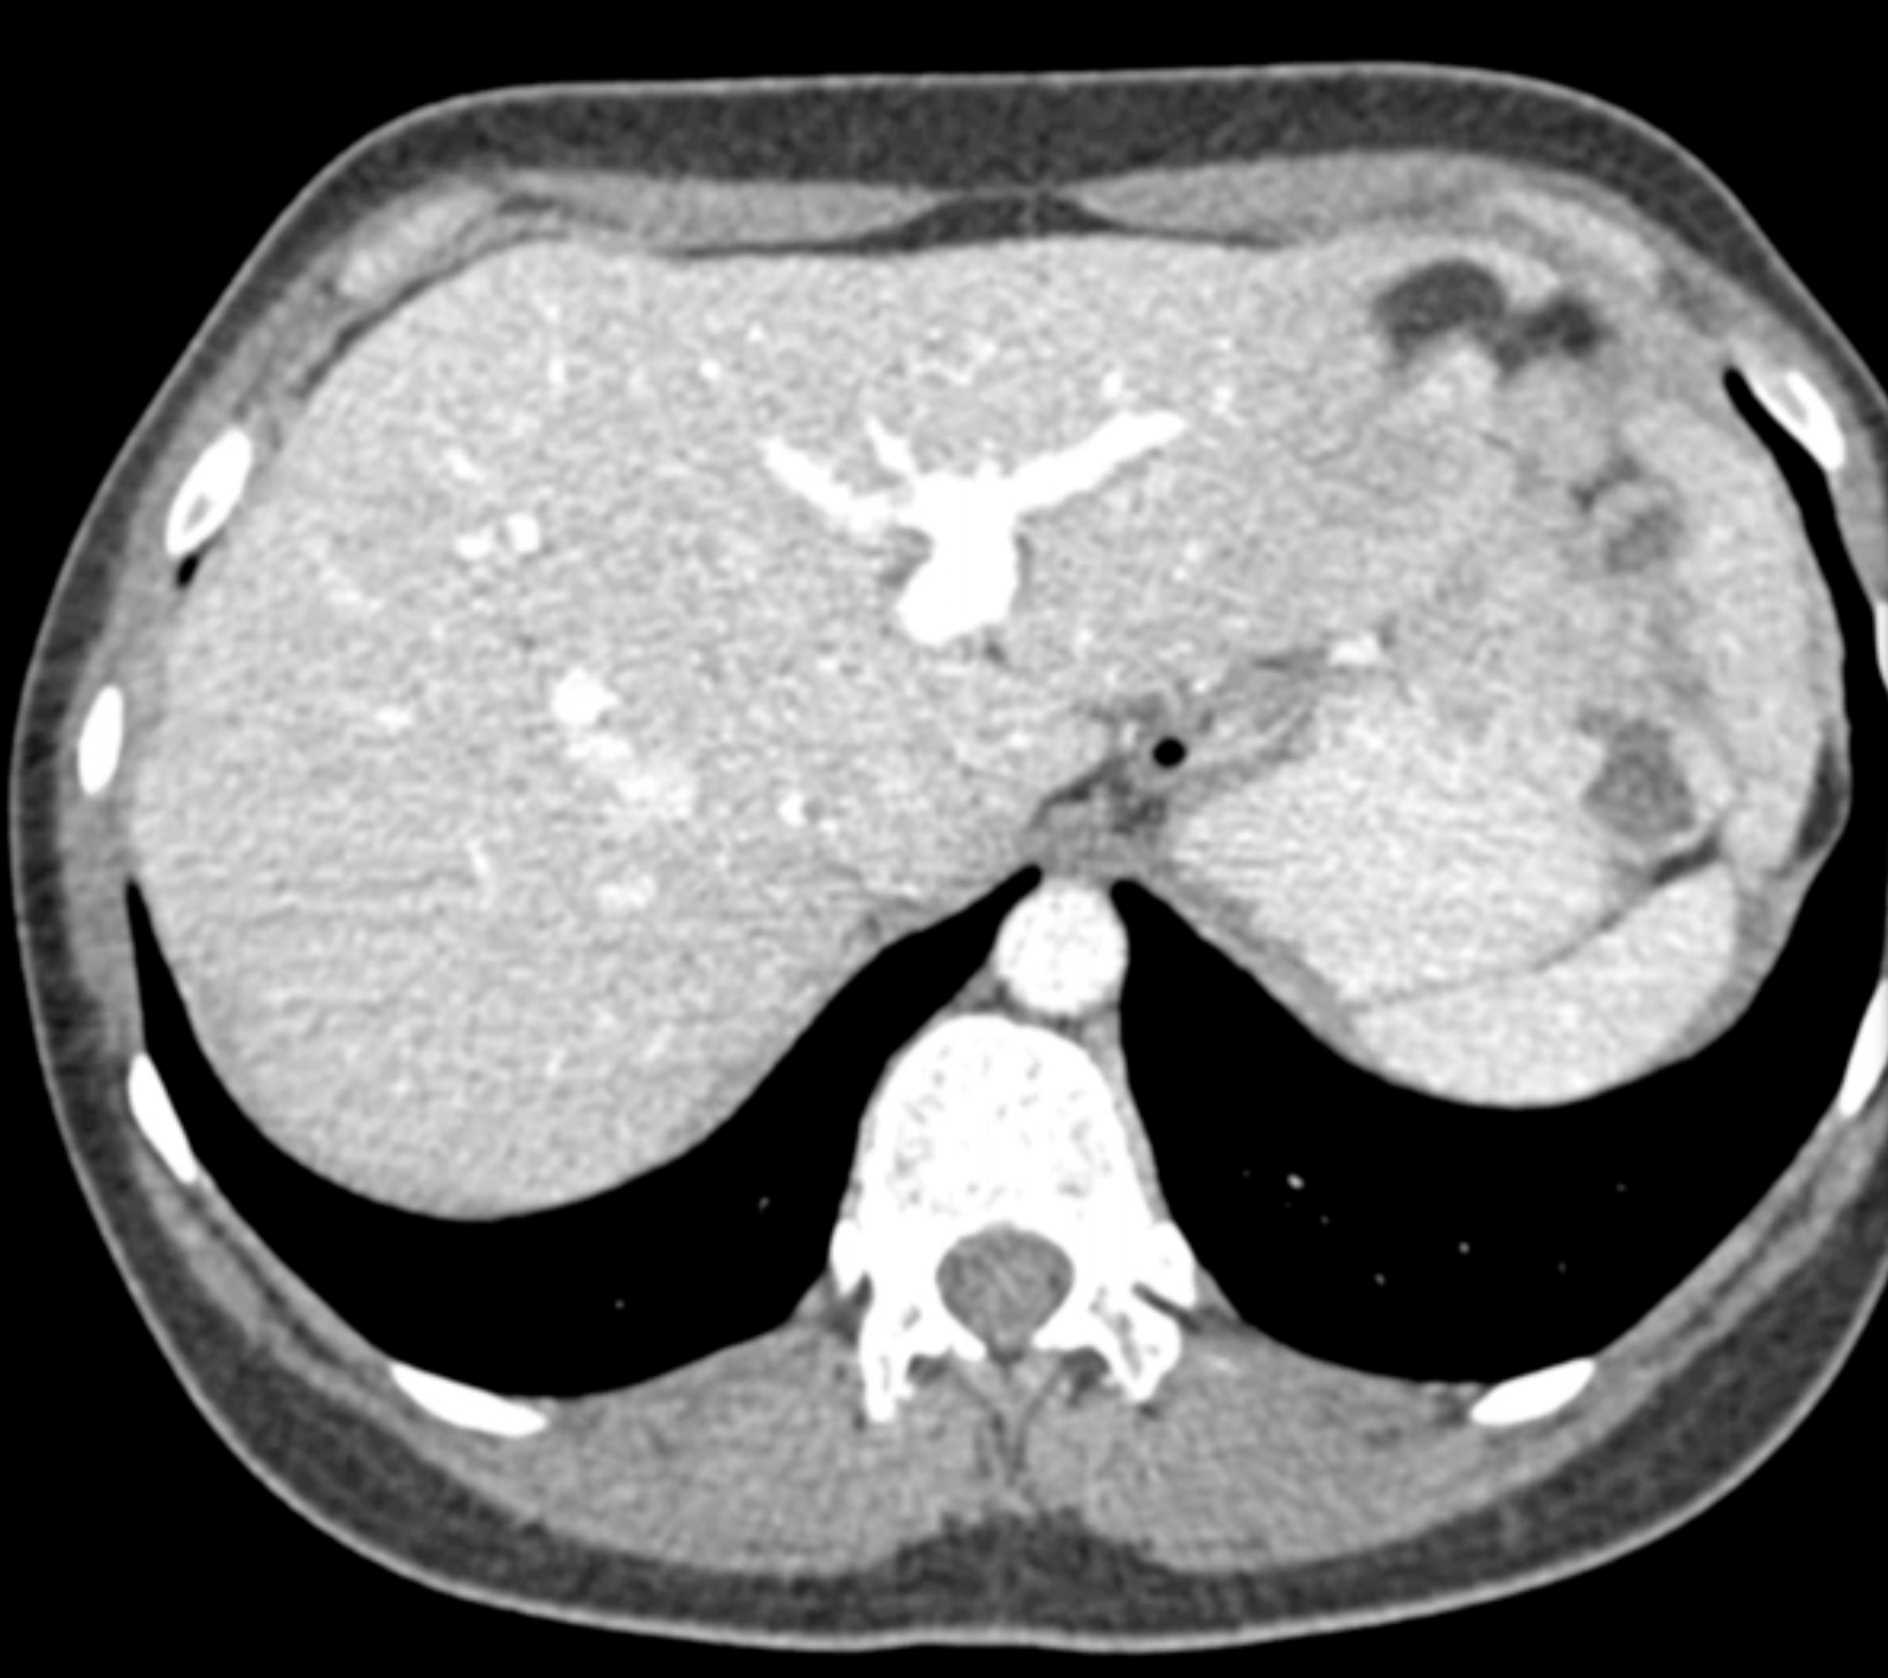

Multiple Gastric GIST Tumors with Spread to Nodes (Carney-Stratakis Syndrome)